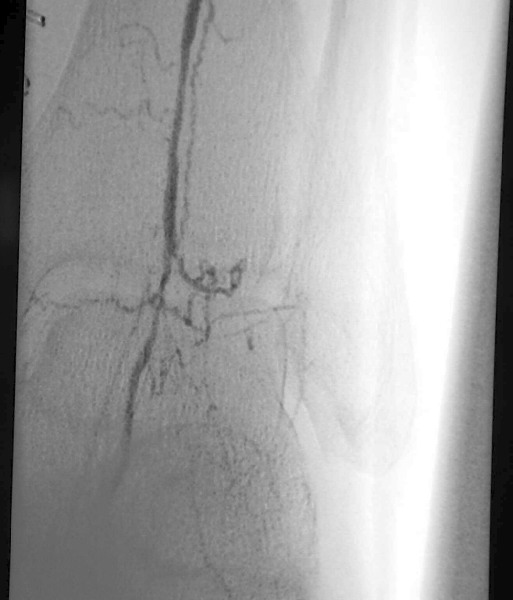

What Did The Angiogram Reveal?

An angiogram revealed extensive tibial peroneal disease on the left limb with occlusion of all vessels to the mid-calf level. There was reconstitution in the anterior tibial that provided dominant flow to the foot and reconstitution of the dorsalis pedis artery. A MRI of the left foot revealed multiple areas of small abscesses associated with the ischemic ulcers but no evidence of osteomyelitis. After the failed bypass, vascular surgeons were consulted and repeat vein mapping confirmed the absence of a usable vein conduit. With the history of aborted left lower extremity bypass, the multidisciplinary team planned for endovascular limb salvage with interventional radiology. Noninvasive vascular testing included TcPO2 of the left pretibial region (49 mmHg) and the left dorsum (30 mmHg). A diagnostic angiogram prior to the aborted surgical procedure revealed a patent abdominal aorta, iliac arteries and left superficial femoral artery. The femoral bifurcation was intact. The above- and below-the-knee popliteal artery also was patent and without stenosis. The posterior tibial artery was occluded at the level of the mid-calf. The peroneal artery was severely diseased. The anterior tibial artery had proximal, hemodynamically significant stenosis and a 30 mm long occluded segment at the level of the lower one-third of the calf. There was hemodynamically significant stenosis of the dorsalis pedis artery at and just below the level of the ankle joint.

After completing angiogram procedures, surgeons performed an antegrade puncture of the left common femoral artery and placed a 6-Fr sidearm sheath with its tip in the proximal superficial femoral artery. A repeat diagnostic study confirmed the previous findings. The team subsequently used a 4-Fr Berenstein catheter with glide coating (Boston Scientific) loaded with a .014-inch guidewire (Sparta/Core 14, Guidant Corp.) to catheterize the anterior tibial artery and cross the stenosis. The vascular surgeons performed cryoplasty therapy with a 3 mm by 20 mm PolarCath Peripheral System balloon (CryoVascular Systems, Inc.). A post-op control angiogram showed excellent results with a less than 10 percent residual stenosis and no angiographic evidence of dissection. The vascular surgeons proceeded to turn their attention toward the occluded segment of the anterior tibial artery. They advanced the 4-Fr glide Berenstein catheter across the aforementioned treated segment and placed the tip of the catheter just above the occluded portion of the artery. After injecting contrast, the surgeons documented reconstitution of the post-obstructed anterior tibial artery. The surgical team crossed the obstructed segment with a 0.035-inch straight, stiff Glidewire (Boston Scientific), advanced the catheter across the obstruction and confirmed its intraluminal position with a contrast injection. Using the 3.0 mm balloon, they treated the obstructed segment with cryoplasty therapy. A post-op control angiogram disclosed minimal residual stenosis and no vessel wall dissection. There was no evidence of distal embolization of plaque fragments. The vascular surgeons advanced the 0.014 inch guidewire through the balloon catheter and crossed the stenosis of the dorsalis pedis artery again, utilizing a roadmap technique. They treated the stenosis of the dorsalis pedis artery at and below the ankle with a 2.5 mm by 20 mm CryoPlasty balloon. A post-op control angiogram showed significant improvement in the diameter of the dorsalis pedis artery with a focal area of spasm at its mid-portion. The patient tolerated the procedure well and the multidisciplinary team noted a strong, palpable dorsalis pedis pulse after the procedure.